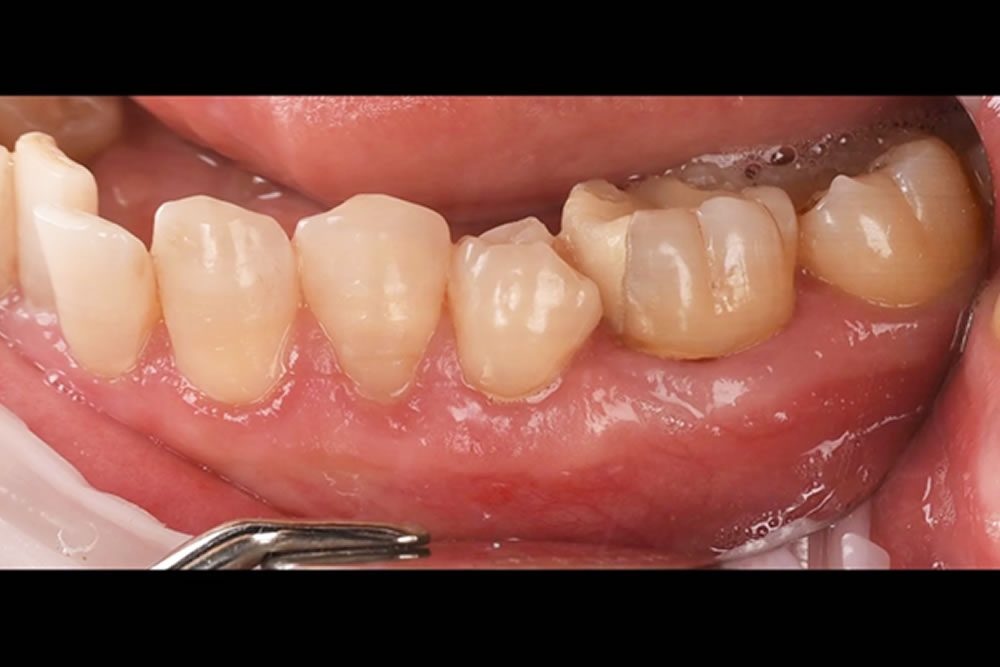

下がった歯茎をマイクロスコープ精密治療・根面被覆術で改善した症例

| 治療期間・回数 | 9ヵ月(治療回数:1回) |

| 治療内容 | ・根面被覆術 ・マイクロサージェリー |